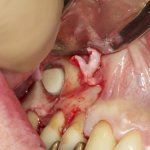

Your surgeon will cut the gum tissue where your back teeth used to be. The tissue is raised, exposing the bone. A small, oval window is opened in the bone. The membrane lining the sinus on the other side of the window separates your sinus from your jaw. This membrane is gently pushed up and away from your jaw.

Granules of bone-graft material are then packed into the space where the sinus was. The amount of bone used will vary, but usually several millimeters of bone is added above the jaw.